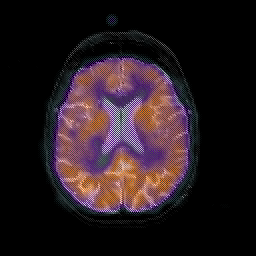

Normal aging, overlay -- Slice #33

[Home][Help][Clinical] Slice 33